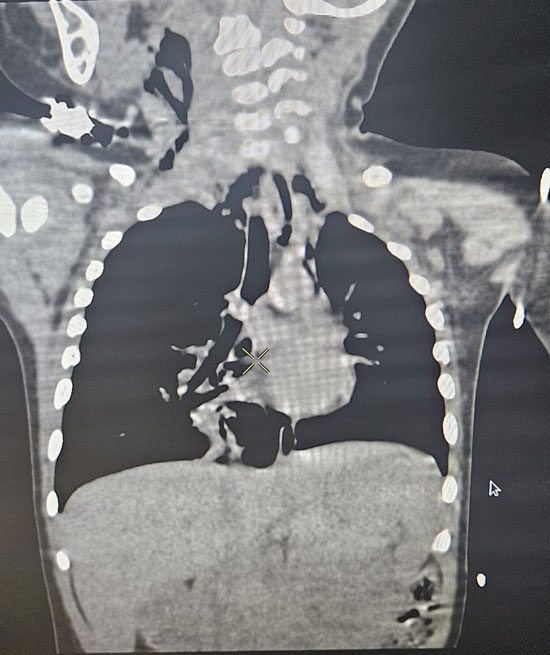

Upon arrival at KMC Hospital, the child was assessed by Dr Swathi Rao, consultant - paediatric intensivist, who immediately recognized the seriousness of the condition. Despite initial hesitation from the family, the child’s respiratory status worsened, with oxygen saturation falling to 88 percent and visible distress. An urgent CT scan of the thorax confirmed a foreign body obstructing the right bronchus, resulting in hyperinflation of the right lung and compression of the left lung and heart.

An expert opinion was promptly obtained from Dr Gautham Kulamarva, consultant ENT surgeon. Despite it being Christmas Eve night, seamless coordination was achieved between the ENT team, operating room staff, the anaesthetist team led by Dr Sunil and Dr Frieda, and the administration teams of KMC Hospital at both Ambedkar Circle and Attavar, enabling all logistics to be arranged swiftly. The child was immediately taken to the operating room at midnight, where Dr Kulamarva performed an emergency bronchoscopic removal, safely retrieving the foreign body obstructing the right bronchus without complications. As nearly 18 hours had elapsed since the incident and early signs of waterlogging had developed in the lungs beyond the obstruction, the child was electively ventilated for a few hours and successfully extubated after six hours.